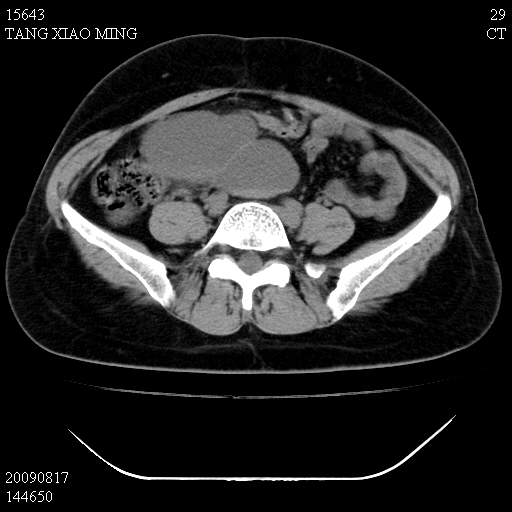

标题: CT21692:盆腔病变

女,33岁,右下腹痛2年余,既往宫外孕病史,如在我院手术,结果下周公布,

可能的诊断。1子宫内膜异位【子宫腺肌症并右卵巢巧克力囊肿】;2 右卵巢囊腺瘤。子宫肌瘤

1)考虑卵巢巧克力囊肿,不排除卵巢囊腺瘤。2)子宫肌瘤可能。

卵巢囊腺瘤,子宫肌瘤,直肠壁厚,不除外占位.